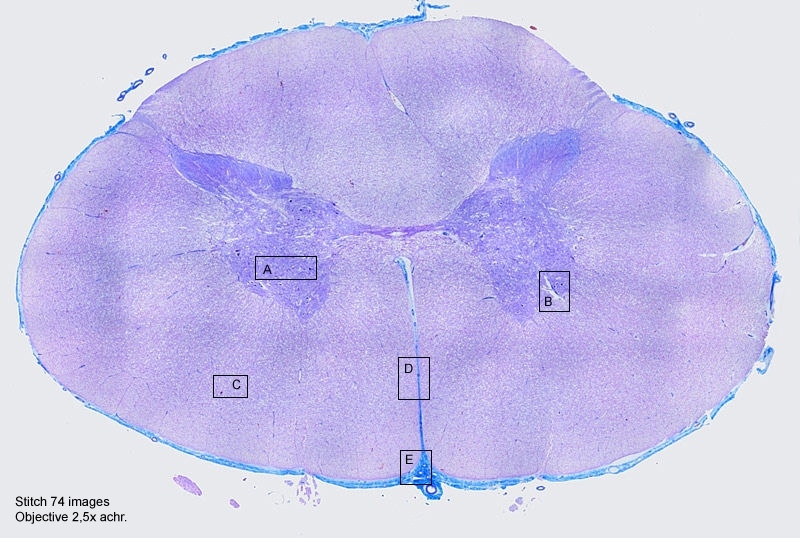

Histologie: Rückenmark

Wer erkennt den Schmetterling :-) ?

Die 12 Einzelbilder habe ich mit autostitch zusammengefügt und anschließend auf Hochglanz gebracht.

Mir ist es nun endlich gelungen ein Bild zusammenzufügen in dem man die dunklen Randbereiche nicht mehr

sieht.

Ich brauchte damals 74 Bilder (den Schnitt ist ungefähr Zwei Zentimeter breit) mit ein 2,5x Objektiv.

Deines ist nur 12 Bilder!!! Wie groß ist dein Schnitt denn? und was für ein Objektiv gebrauchst du?